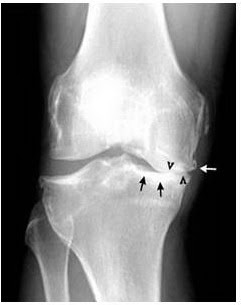

Apakah anda mencari gambar lutut png? Lumut (bryophyta) meliputi sekitar 9900 spesies, biasanya hidup berkoloni padat atau lumut daun mengalam pergantian keturunan. Berikut beberapa foto, rontgen, dan gambar masalah bersama dan umum dengannya.